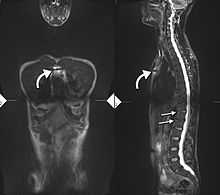

34-year-old male with AS. Inflammatory lesions of the anterior chest wall are shown (curved arrows). Inflammatory changes are seen in the lower thoracic spine and L1 (arrows).

Ankylosing spondylitis is a member of the more broadly defined disease axial spondyloarthritis.[17] Axial spondyloarthritis can be divided into (1) radiographic axial spondyloarthritis (which is a synonym for ankylosing spondylitis) and (2) non-radiographic axial spondyloarthritis (which include less severe forms and early stages of ankylosing spondylitis) [17]